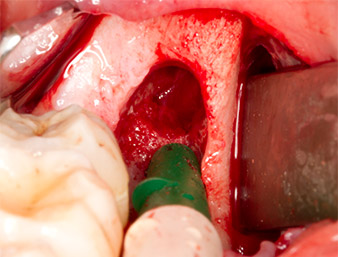

The tissue above the root remnant was not completely ossified and consisted for the most part of granulation tissue modified by inflammation (Fig.4).

To obtain autogenous material for subsequent wound treatment, healthy bone chips were harvested from the surroundings of the root remnant with a piezo surgical instrument (Piezomed B5) (Fig. 5).

The autogenous tissue was removed with the scraper-shaped section of the working part of the instrument and stored in a physiological saline solution until further use (cf. Fig. 13).